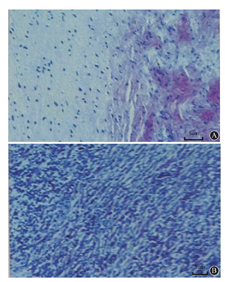

A:主动脉窦瘤;B:右纵隔肿物(HE染色,×100)

患者男性,24岁,因"间断胸痛、发热1月余"于2016年9月19日入院。入院1个月余前睡眠时无明显诱因突发右前胸撕裂样疼痛,持续约半小时后自行缓解,未予重视。数天后出现咳嗽、咳白色泡沫痰,后出现发热,伴畏寒、寒战、肌肉酸痛,体温每日上午正常,下午升高至39℃左右,偶有活动后心悸、胸闷,休息5~6 min可缓解,伴乏力,活动耐量较前下降。于当地医院查胸部CT(2016年8月5日)示:右下肺门旁囊实性占位性病变,考虑良性;心脏大。予阿米卡星抗感染治疗效果不佳,体温峰值升至39.8℃。2016年9月2日查血常规未见异常,高敏C反应蛋白84.1 mg/L,血培养两次均阴性。超声心动图:LVEF 54%,主动脉无冠窦呈一囊袋状结构向右房膨出,顶部可见破裂口,主动脉无冠窦向右房持续分流;全心大,肺动脉内径增宽,心包腔内可见少量液性暗区。2016年9月6日复查超声心动图示:靠近外口窦部后壁可见一偏强回声,测范围约10 mm×6 mm。联合心外科会诊,考虑"感染性心内膜炎,瓦氏窦瘤破裂",予万古霉素+亚胺培南抗感染治疗,患者体温峰值逐渐降至正常,入我科前2 d体温峰值再次升高至37.5℃,为进一步诊治收入我科。患者病程中无咯血、盗汗,无活动后喘息及下肢水肿,无皮疹、关节痛。既往体健,否认幼年时活动后呼吸困难、发绀、蹲踞病史,否认幼年关节肿痛、肾炎病史。未婚,曾服兵役3年,家族史无特殊。体格检查:体温37.6℃,脉搏123次/min,呼吸17次/min,血压148/76 mmHg。身高183 cm,体重78 kg。皮肤黏膜无黄染,双肺未及干湿啰音。心尖搏动弥散,叩诊全心增大,心率123次/min,律齐,三尖瓣听诊区可闻及3/6级舒张期杂音。腹软无压痛,肝脾肋下未及。双下肢无水肿。入院诊断:主动脉窦无冠窦窦瘤破裂,感染性心内膜炎?全心扩大,主肺动脉扩张,心包积液(少量),左心功能减低。入院后完善化验检查:血沉63 mm/第1小时,C反应蛋白19.6 mg/dl,降钙素原0.16 ng/ml,肌钙蛋白T 0.007 ng/ml,肌酸激酶-同工酶1.02 ng/ml,B型利钠肽217.60 pg/ml。心电图示窦性心动过速,各导联波形未见明显异常。复查超声心动图:各房室内径大,主动脉窦无冠窦瘤样改变,向右房膨出,窦瘤顶部连续性中断约8 mm(图1A)。心包腔内后区探及宽约9 mm液性暗区,LVEF 48%。多普勒:主动脉无冠窦可探及五彩血流分流至右心房(图1B),收缩期为著,流速最高4.8 m/s。心脏MRI:无冠窦呈囊袋样突向右心房,并可见向右心房分流,结合超声心动,符合无冠窦瘤破裂;左、右心室及右心房增大;LVEF 46.8%,心包积液(中量)。予万古霉素+亚胺培南抗感染治疗,患者体温峰值降至38.5℃以下。2016年9月20日转入心脏外科继续原方案抗感染治疗,2016年9月26日行主动脉窦瘤破裂修补术+右胸腔肿物切除术,术中见心包内中量淡黄色积液,右心房室扩大,主动脉无冠窦瘤破入右心房,瘤蒂根部直径约1 cm,未发现明确赘生物。右胸腔肿物质硬,直径约6 cm,边界清。术后当天体温即降至正常(诊疗过程体温及心率变化见图2)。手术病理结果:右胸腔炎症性肌纤维母细胞瘤,WHO ICD-0编码I级(属于交界性或恶性潜能未定肿瘤)。主动脉窦瘤致密纤维组织,间质明显玻璃样变性,伴片状钙化,结合临床符合主动脉窦瘤(图3)。术后复查超声心动图(2016年10月9日):左室内径大(较前缩小),内未见异常回声团,主动脉窦无冠窦回声增强,未见连续性中断,心包腔内未探及液性暗区。多普勒:主动脉无冠窦修补处未探及分流。出院诊断:主动脉窦无冠窦窦瘤破裂修补术后,左室扩大,主动脉瓣关闭不全(轻),右胸腔炎症性肌纤维母细胞瘤切除术后。